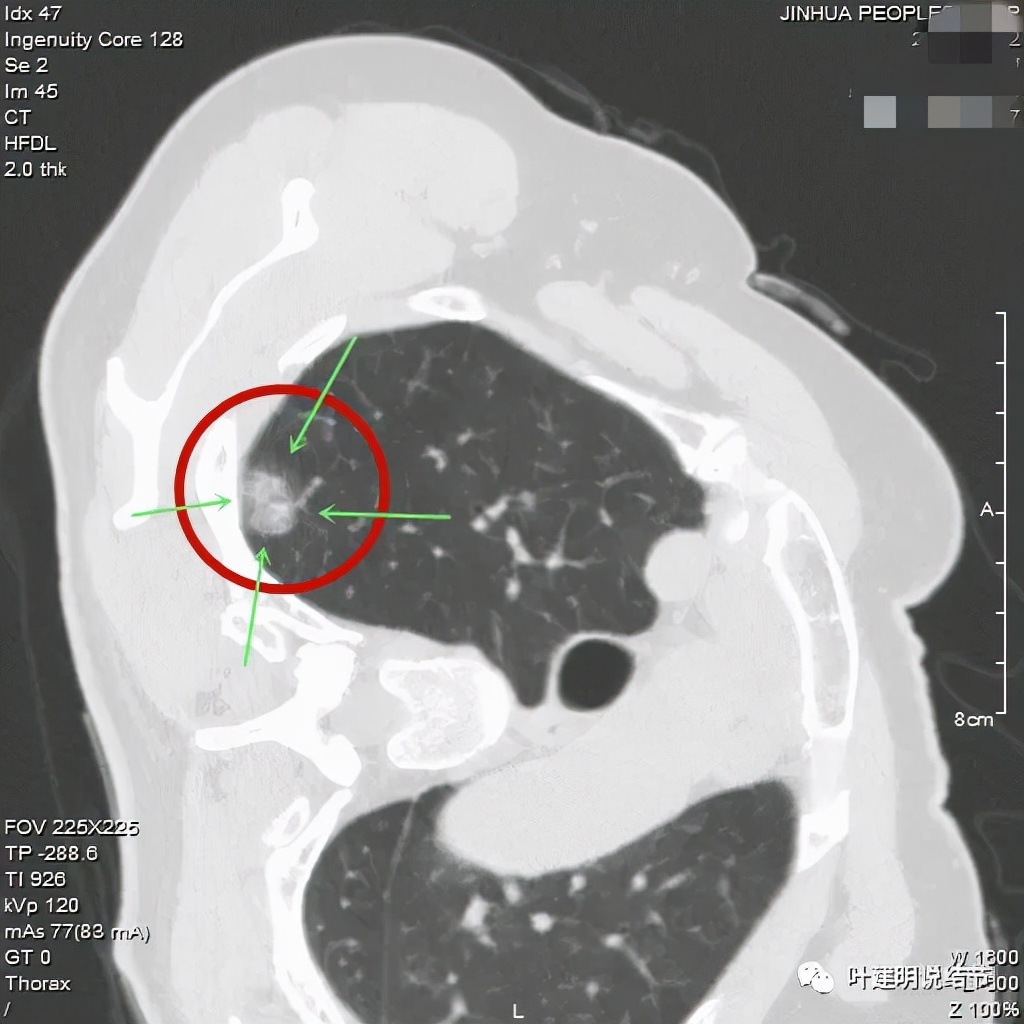

金华的某A,女性,今年43岁,检查发现左肺上叶结节2月余。其于当时说是在外院检查发现,到我门诊找我看过的(我是记不清楚了),大概是告诉她:考虑早期肺癌可能性大,但密度还低,边缘显模糊。让她再随访观察下再决定手术与否。这次送孩子上大学后,她马上来医院全面检查并若需要手术就决定手术了的。我们先来看她的平扫片子:

可见左肺上叶磨玻璃结节,边缘略显模糊,瘤肺边界不是很清,但总体上看,病灶轮廓仍是较为清楚的,而且有所层面有微小血管进入,病灶密度也不均匀,感觉有点杂乱。这种病灶如果随访了2个多月仍持续存在,也没多少变化的话,基本上要考虑肿瘤范畴的结节。为了看细节,我们建议其再查了靶扫描,图像如下:

病灶密度较低,膨胀性略,瘤肺边界在靶扫描上还是显得有些清晰的